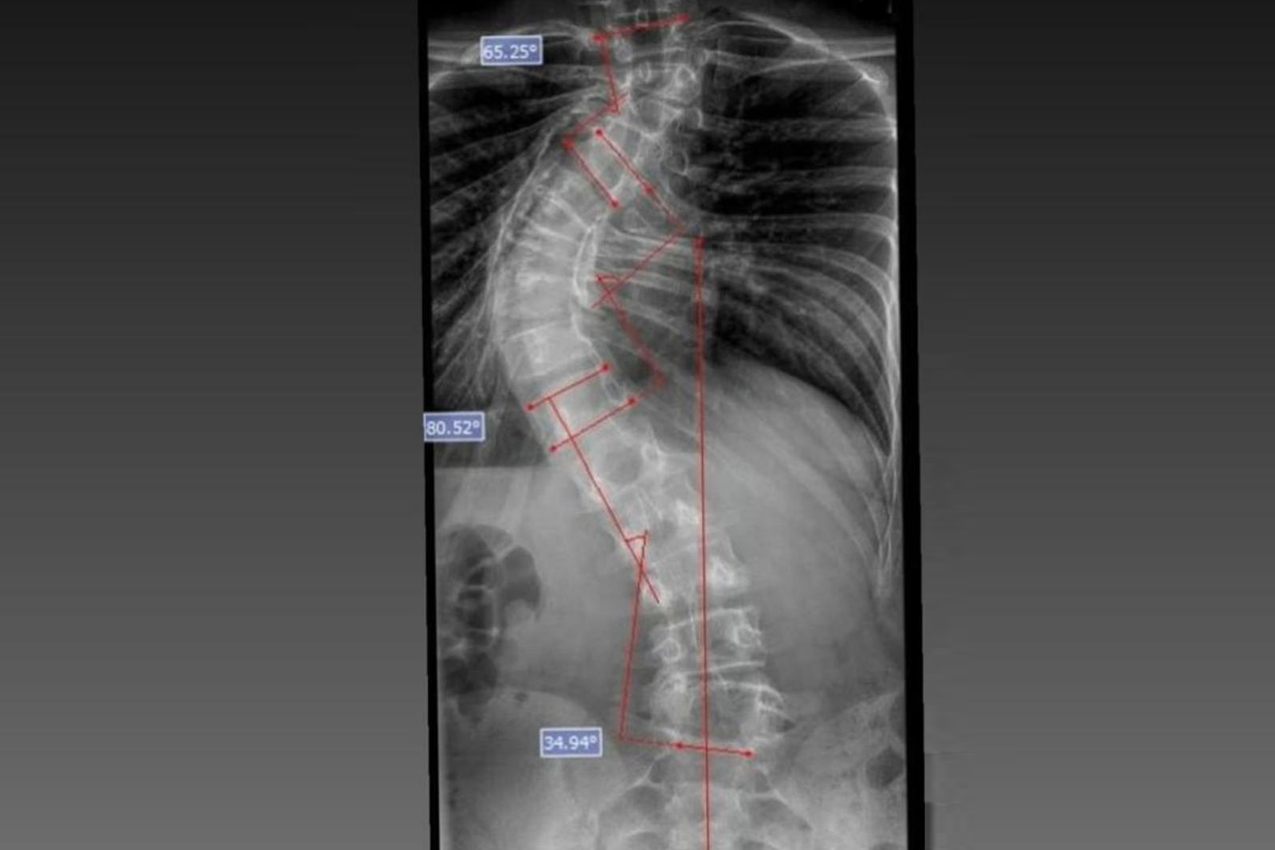

Laura era portadora de escoliose e, em agosto de 2025, realizou a cirurgia de correção da coluna, o que lhe permitirá ter uma vida normal de agora em diante. Moradora de Bom Sucesso do Sul, região Oeste do Paraná, é acostumada a andar a cavalo, mas com o problema na coluna a prática estava longe de ser prazerosa.

“Eu vim de Londrina para cá com ótimas recomendações. Vim no dia 4 de junho de 2025. Pensei que sairia frustrada mais uma vez. Tinha ouvido 'não' a minha vida inteira. Quando cheguei, o doutor João disse que o meu caso era difícil, mas que não iria desistir porque gostava de desafios e sabia que daria certo. Saí daqui radiante, porque sabia que ia acontecer”, relembrou Joyce.

A cirurgia ocorreu no dia 28 de julho e uma segunda etapa em quatro de agosto. Desde então, Joyce viu a sua vida mudar. “Nasci com a escoliose e tinha muita dificuldade e limitações para caminhar e perda de movimento. Havia dias em que eu não levantava da cama. Quando saia de casa recebia olhares de julgamento das pessoas, que era o que mais me incomodava. Depois da cirurgia, posso dizer que eu tenho uma nova vida. Eu venci a batalha”, relatou.